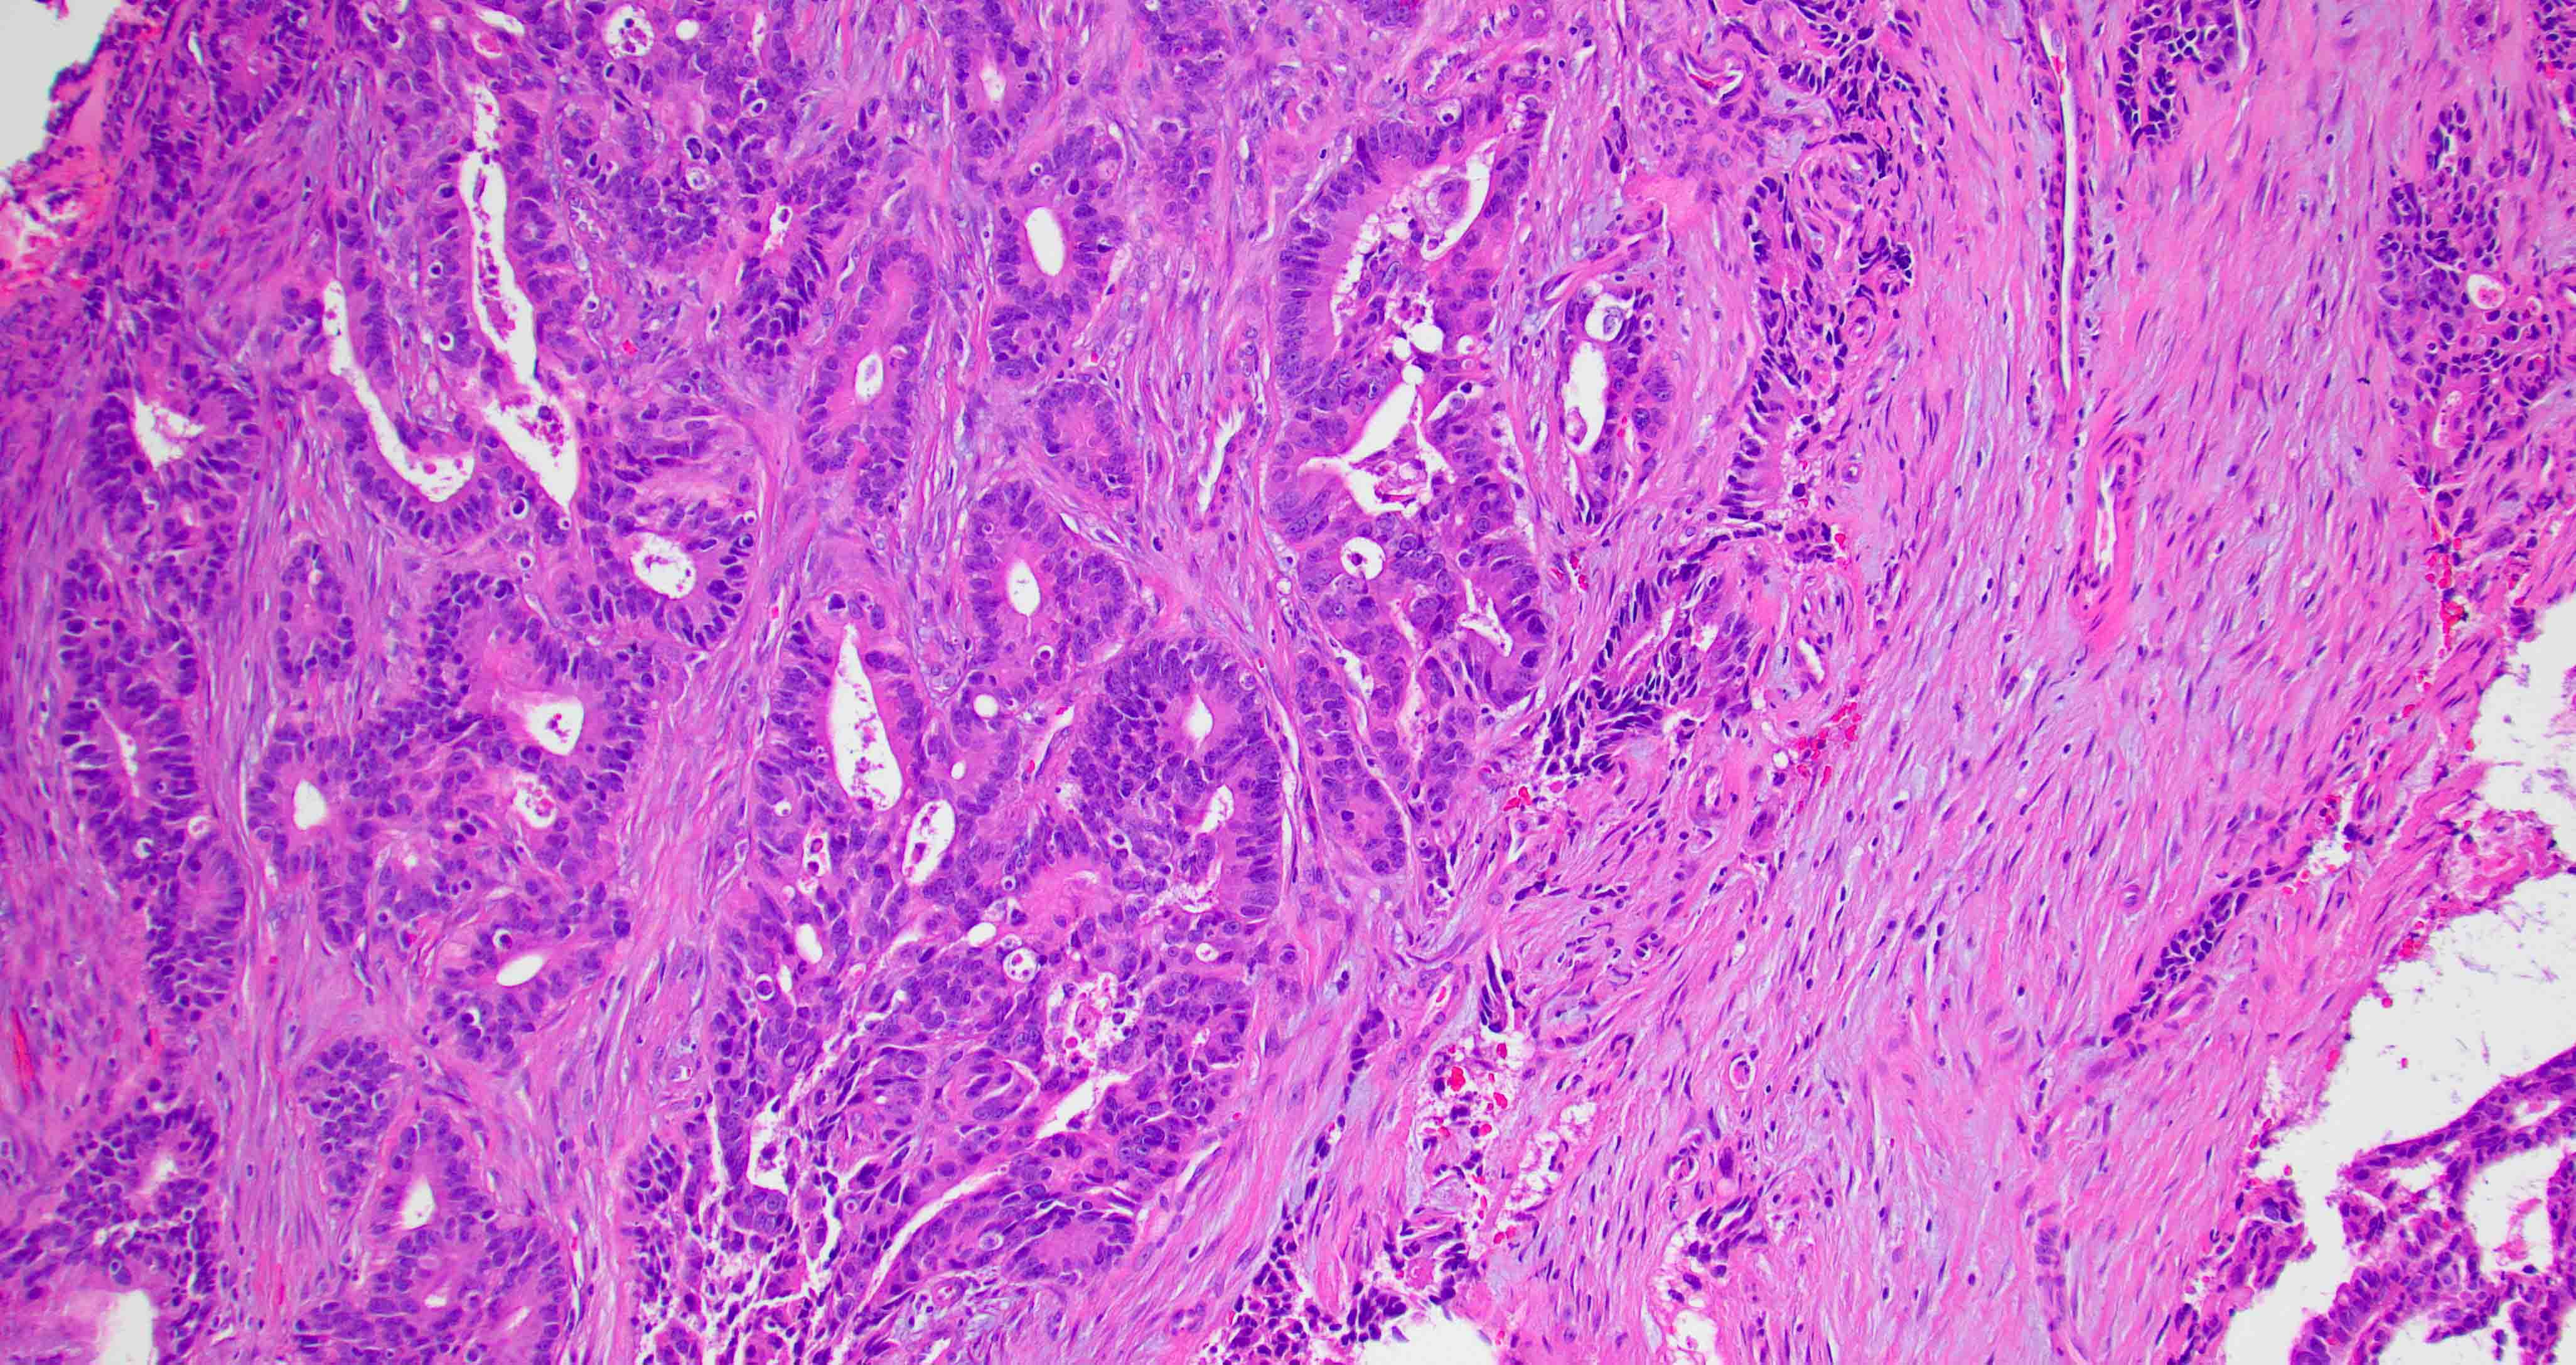

Microscopic (histologic) images

Contributed by Diana Bell, M.D.

Intestinal adenocarcinoma (ITAC)

Nonintestinal adenocarcinoma (non-ITAC)

- ITAC displays glandular, tubular and trabecular architecture and few papillae and resembles a conventional colorectal adenocarcinoma

- Low grade non-ITAC can exhibit exophytic papillae, tubular or glandular, trabecular, cribriform, clear cell and mucinous patterns

- Papillae and glands are usually lined by a single layer of uniform columnar or cuboidal cells with eosinophilic cytoplasm and slight cytologic aberrations